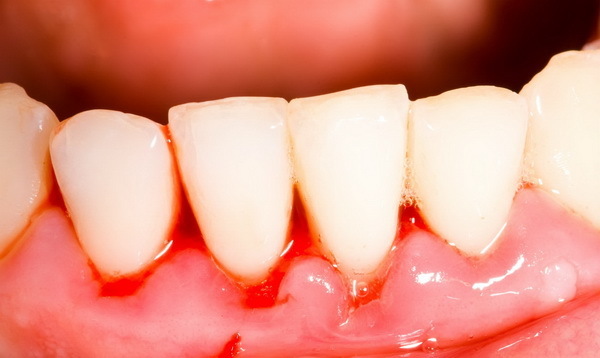

- Локализованный (очаговый) пародонтит — воспаление поражает один или несколько зубов, а также ткани, прилегающие к ним. Чаще всего протекает в острой форме. При отсутствии лечения переходит в диффузный пародонтит, заражая здоровые зубы.

Фото 2. Локальный пародонтит. Воспалены несколько зубов, в области воспаления наблюдается кровотечение.

- Генерализованный (диффузный) пародонтит — воспаление поражает весь зубной ряд или практически все зубы, а также ткани, прилегающие к ним. Чаще всего протекает в хронической форме. Нередко приводит к потере зубов.

Внимание! В начале заболевания, распространенность обычно локализованная. Именно в этот период важно проконсультироваться со специалистом и начать лечение. Вылечить пару зубов будет проще и быстрее, чем весь зубной ряд.